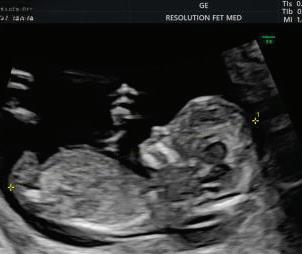

2. NUCHAL TRANSLUCENCY (NT) SCAN

• Done @11–13+6 weeks.

• CRL 45–84 mm.

• This is the cornerstone of first trimester screening.

1. NT is the sonographic appearance of subcutaneous accumulation of fluid behind the fetal neck, below the skin in the first trimester of pregnancy.

2. Measured in mid-saggital section only.

3. Measured between 11-14 weeks.

4. CRL between 45-84mm.

5. Magnified to include only head and upper thorax.

6. Fetus should be in neutral position.

7. Demostrate fetus separate from amnion.

8. Measurement should be ON to ON (cross bar of the callipers should be such that it’s hardly visible and merges with white line, not nuchal fluid).

During the scan more than one measurement should be taken and maximum value should be considered.